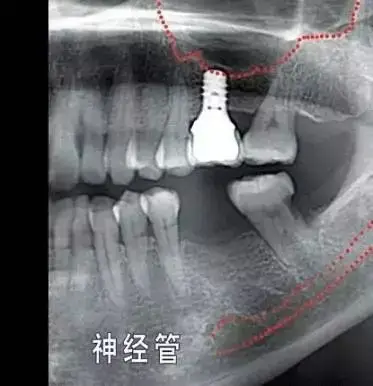

种植牙有多少不为人知的秘密